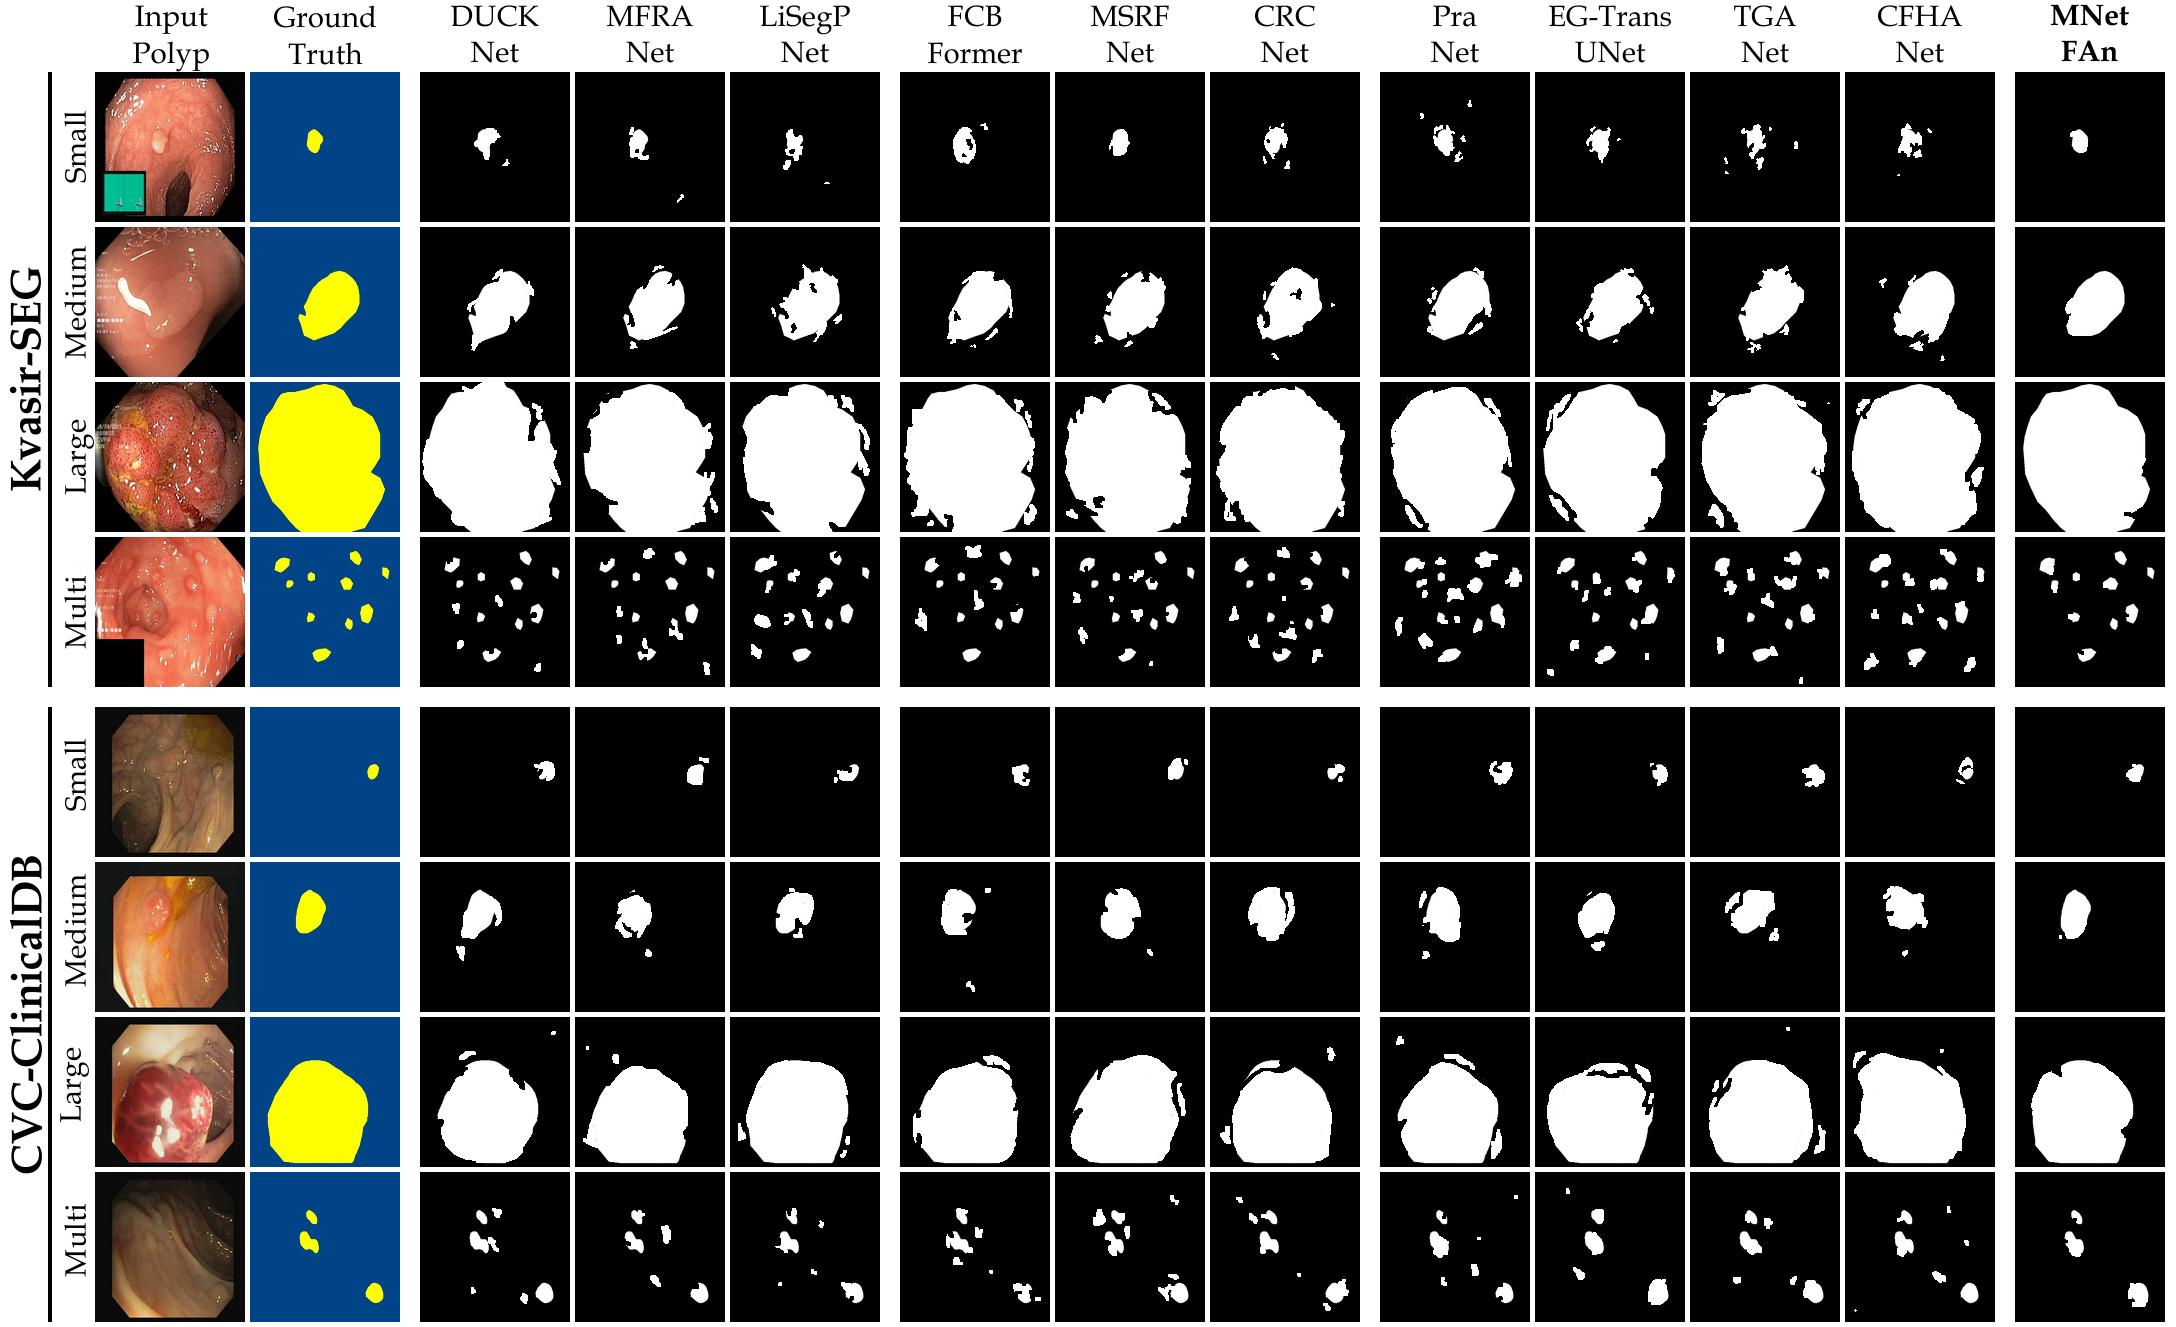

Qualitative Evaluation

Fig. 7 offers qualitative validation, showcasing MNet-SAt’s superior polyp mask generation compared to baselines across four cases. This qualitative superiority aligns with the previously established quantitative results. In the case of small polyps (first and fifth rows), all baseline methods initially appear to produce satisfactory visual results. However, upon closer inspection, they fail to maintain fine boundary details. Our framework excels in preserving polyp anatomy and topology for medium and large polyps, significantly outperforming the baseline methods. Notably, even in multiple polyps, our framework successfully captures more polyps and approximates the ground truth more closely. The primary reason for this superior performance is the EGFE module, which effectively eliminates noise in conjunction with the HMAtt module, resulting in a few false positives. Our analysis reinforces MNet-SAt’s effectiveness in handling challenging polyp scenarios (small, medium, large-scale, and multi-polyps) while suppressing non-regions of interest.